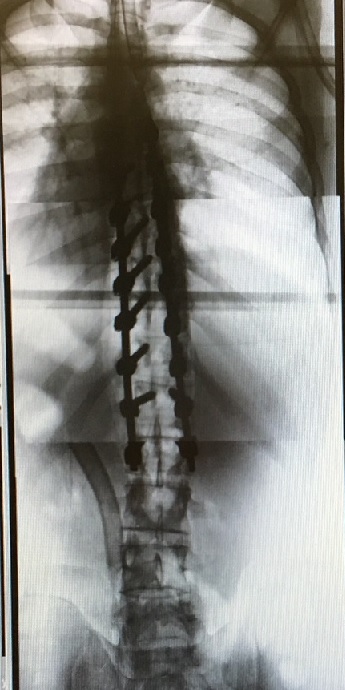

I wasn't going to post anything about this but since my wife and son have already put it all over social media, I suppose that it won't hurt.  My son Max is affected with a fairly serious back condition called scoliosis.  We've been watching his back X-rays for several years now, and according to the back specialists it had gotten to a point this year where a surgical repair was necessary, in order for him to avoid a lifetime of back pain.  Max just graduated from high school and will be starting college in the fall, so we decided now was the time to have the surgery.

The surgery was on Monday and went well, thankfully, but I have to admit to being shocked and awed by the X-rays taken afterwards.  Here's a "before" X-ray of Max's back:

Holy crap!  FYI those 18 screws are 45-50 millimeters long (50 millimeters is 2 inches), and 6 millimeters in diameter (about a quarter inch).  The two stainless steel rods are 12 inches in length.  Max now has two scars on his back over a foot long.  He was almost 6'2" when he went in, but we expect him to be 6'3" to 6'4" when he comes out.